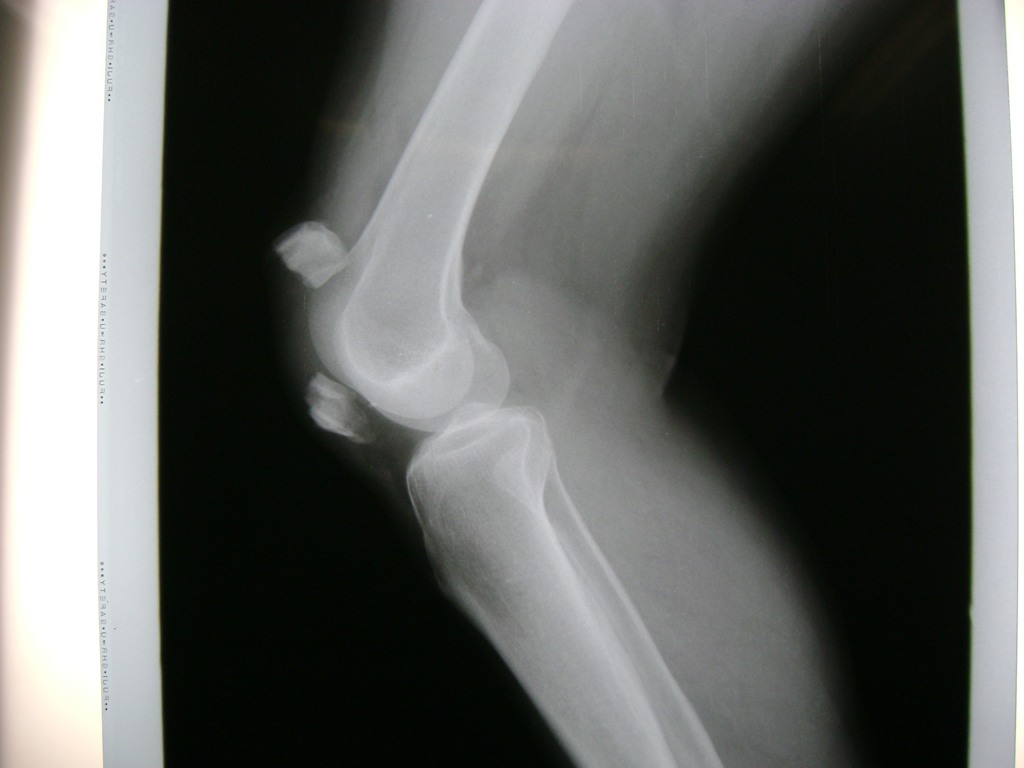

Fémur - Rodilla

La artroscopia de rodilla es un cirugía en el cual la estructura interna de la articulación es examinada ya sea para realizar un diagnostico o para realizar un tratamiento, este procedimiento se realiza utilizando un instrumento parecido a un pequeño tubo llamado artroscopio.